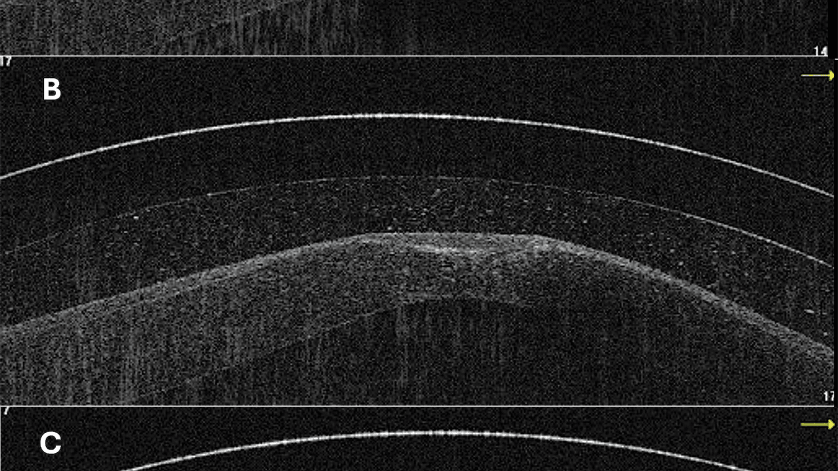

Scleral Lens Simplicity: Utilizing Anterior Segment OCT for Scleral Lens Fitting